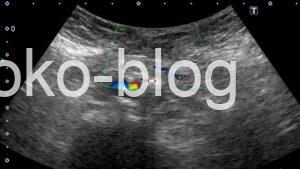

カラードプラで観察してみましたがのらず

腸管が皮下に見えるってことはヘルニアかな、カラーものらないから嵌頓の可能性もあるかなと医師に報告。